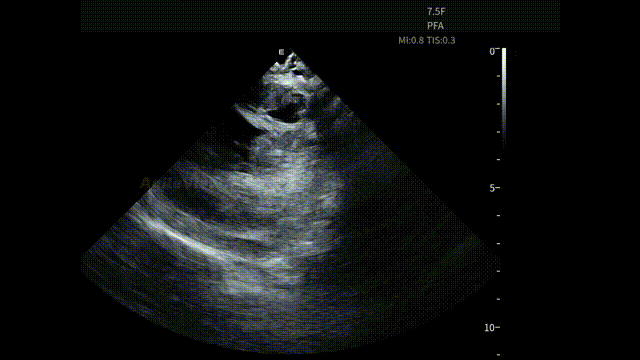

ICE 的实时成像有助于术者更加直观地理解心腔内部结构,对于提升消融手术的精细化程度和整体质量非常有帮助。这款AgileView™ ICE 采用全球最细的 7.5Fr 设计,在心房内操作时存在感更低,尤其是在多导管同时使用的场景下,更有利于操作空间的管理。

手术开始后,AgileView™ ICE 导管作为术中影像辅助工具,经股静脉穿刺进入心房。考虑到本台手术将搭配PulseSelect™消融导管使用,助手将ICE主机调整至“PFA预设模式”,便于后续更直观的判断导管贴靠情况。通过 HomeView 视角,术者首先了解了患者心腔整体结构,为操作提供统一的影像参考。

HomeView

随后,ICE对左心房、左心耳及心包区域进行系统性扫查。术前重点评估左心耳内是否存在血栓形成,并同步观察心包情况,确保在消融前,关键风险已被充分排查,为保证手术安全提供直观依据。

在全球最细 7.5Fr ICE的持续影像引导下,术者完成房间隔穿刺。AgileView™ ICE实时显示房间隔 tenting及穿刺针跨隔过程,使穿刺路径和深度判断更加明确。穿刺成功后,PulseSelect™导管顺利进入左心房,整体操作节奏紧凑。

进入消融阶段后,AgileView™ ICE 持续提供近场实时影像,动态显示消融导管与心房组织之间的空间关系与贴靠状态。在肺静脉隔离过程中,ICE 下可清晰观察到导管在左上、左下、右上及右下肺静脉口部的贴靠情况,为能量释放位置的确认提供直接影像依据。

针对 PFA 能量的物理特性,AgileView™ ICE 配备PFA专属预设成像模式,通过针对性的参数设置,使术中影像更贴合脉冲消融的操作需求,帮助术者更直观地观察导管与组织的贴靠情况,为术中判断提供稳定清晰影像支持。